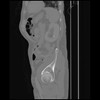

7 CUERPO,CE,Sagittal,3.000,CUERPO,Sagittal,